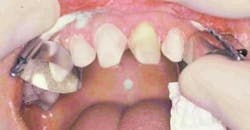

In preparation for the gumlift, a periodontal probe was used to verify that sufficient gingiva could be removed without violating the biological width (Figure 9). Anesthesia was supplemented with injections of 1:100,000 epinephrine injections into the affected area to provide hemostasis during contouring. The Bident straight wire tip (tip No. 3303) was used under constant water flow to excise inflamed tissue between No. 9 and No. 10 and to create esthetic, symmetrical gingival contours (Figure 10). With the Bident, tissue shrinkage is eliminated through less heat and current spread, greatly increasing post-operative comfort and patient healing. The resulting gumlift leaves healthy, symmetrical gingival sites that are ready for clean impression taking.

Once optimal gingival contours were achieved, preparation of the teeth continued. Incisal reduction was achieved using the coarse football diamond (Figure 11) to create a butt joint. The preparations were smoothed using the superfine tapered diamond (836V-1) (Figure 12). Adequate reduction was verified using the thin transparent Preparation Guide, made from the image-inspired wax-up. By checking all surfaces with the periodontal probe through the appropriate holes in the seated preparation splint (Figure 13), you can substantially enhance your success with porcelain restorations of adequate thickness and resistance. Finally, all sharp line angles were smoothed using the Shofu snap-on discs (Figure 14), further increasing resistance and strength. When the preparations were complete, an Impregum Soft polyether impression was taken (Figure 15).